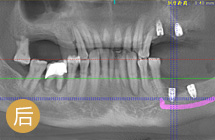

手术成功原理:针对缺牙引起牙槽骨萎缩吸收的情况,通过GPR植骨和保持位点手术形成新的牙槽骨。再通过数字化种牙完成前牙美学区的植入,实现即刻负重,拥有良好的美学效果… [详细]

前牙美学度高

植体结合稳固

术后就能吃饭

远期成功率高